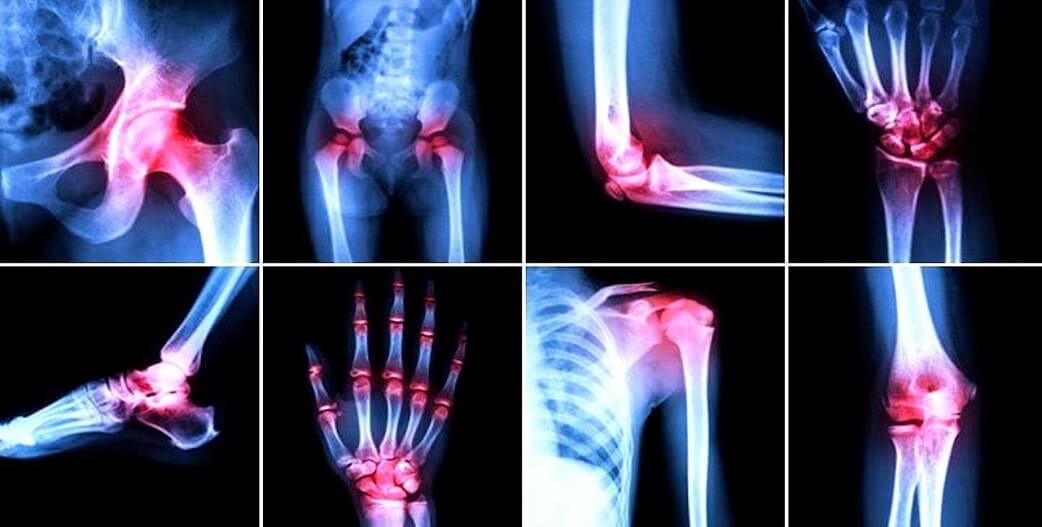

Ορισμένοι άνθρωποι ταλαιπωρούνται όταν μεγαλώσουν από έντονο πόνο στις αρθρώσεις, ο οποίος ταλαιπωρεί και δυσχεραίνει τις καθημερινές δραστηριότητες των πασχόντων. Αυτός ο πόνος οφείλεται στην κακή λειτουργία του χόνδρου, του ιστού βρίσκεται στα άκρα των οστών και αναλαμβάνει την απορρόφηση των κραδασμών.

Για παράδειγμα, τα εκ γεννήσεως ατελώς σχηματισμένα οστά, ο εκ φύσεως ασθενέσθερος χόνδρος, η παχυσαρκία, η υπερβολική επιβάρυνση και οι τραυματισμοί είναι μερικοί από τους λόγους που μπορούν να οδηγήσουν σε δυσλειτουργία του χόνδρου, βλάπτοντας παράλληλα τις αρθρώσεις.

«Όταν ο χόνδρος εκφυλίζεται, το σώμα σχηματίζει οστεόφυτα, που δημιουργούν τριβές μεταξύ τους, προκαλώντας πόνο. Πρόκειται για μια αντίδραση του οργανισμού στο κύριο ζήτημα, την εκφύλιση του χόνδρου. Η απλή αφαίρεσή τους δεν αντιμετωπίζει το πρόβλημα, εκτός από πολύ σπάνιες περιπτώσεις», εξηγεί ο δρ. Sanchez-Sotelo.